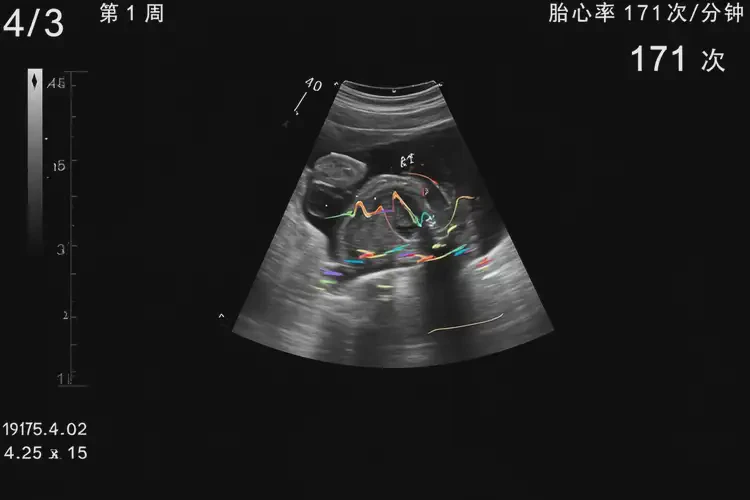

懷孕第1周胎心率171還能保住嗎

胎心率171次/分鐘在懷孕第1周屬于正常范圍

懷孕第1周的胎心率在171次/分鐘是正常的,因?yàn)樵谠性缙冢旱男呐K尚未完全發(fā)育,心率通常較快。胎心率的正常范圍會(huì)隨著孕周的增加而變化。

1. 孕早期(1-12周):胎心率通常在150-190次/分鐘之間,平均約為170次/分鐘。